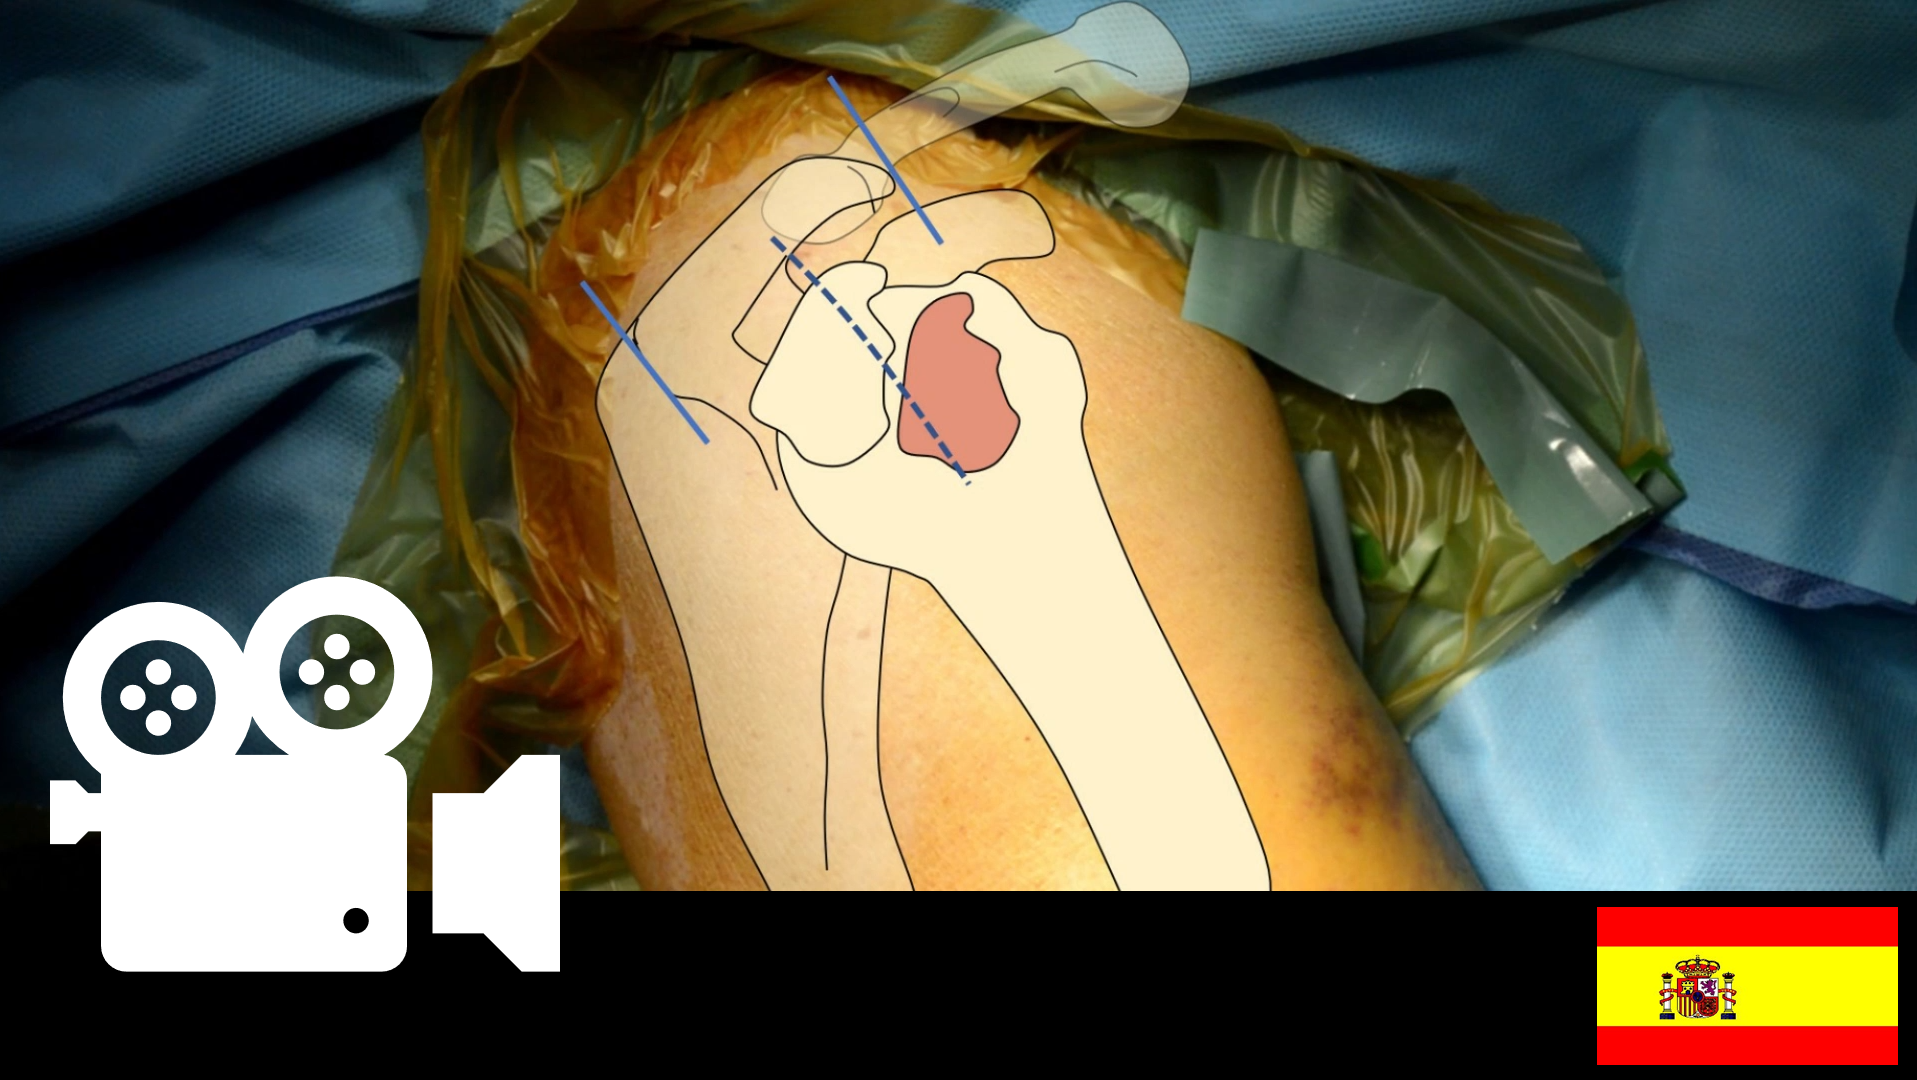

Fractura de Tuberosidad Mayor de Húmero Proximal con Lesión de Manguito Rotador: Reducción Abierta, Fijación Interna y Reparo de Manguito.

Fractura de Tuberosidad Mayor de Húmero Proximal con Lesión de Manguito Rotador: Reducción Abierta, Fijación Interna y Reparo de Manguito.

Videoteca Quirúrgica: Fractura de Tuberosidad Mayor de Húmero Proximal con Lesión de Manguito Rotador: Reducción Abierta, Fijación Interna y Reparo de Manguito.

Síntesis: Paciente presenta lesión de tuberosidad mayor del húmero proximal asociado a lesión de manguito rotador luego de una luxación anterior de hombro. Se realiza un abordaje lateral transdeltoideo de hombro. Luego reducción y osteosíntesis de la tuberosidad mayor con tornillos canulados de 4.5 mm y reparo de la lesión del manguito rotador.